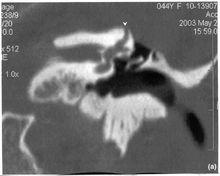

高分辨CT掃描(冠狀位),顯示右側SSCD100年以前人們就知道某些病理情況下,強聲或壓力傳至內耳可誘發前庭症狀。例如,由聲音導致眩暈或眼震的Tüllio現象可出現於下列疾病:外淋巴瘺、梅尼埃病、膽脂瘤中耳炎、迷路炎、內耳梅毒和Lyme病等。

對有症狀及前庭與聽覺功能檢查有異常,疑似SSCD者,高分辨CT有助確診(圖33-2)。CT應取水平位與冠狀位,而以三維重建的顯示率最高,高分辨CT可減少誤診率,有人報告6例用1.0 mm層厚CT掃描提示為SSCD,而用0.5 mm層厚螺鏇CT顯示上半規管頂部存在完整的薄層骨質,否定骨管裂。Branstetter等(2006)對27例疑似SSCD及對照組27例作CT檢測,認為顳骨冠狀位多層斜位重建CT足以顯示SSCD。Krombach等(2006)對26例上、後半規管裂作高分辨MRI,表明T2加權三維重建、最大密度投影和容積成像可以清晰顯示半規管裂的部位。